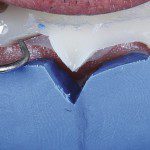

É realizada a inserção do Pro-Retract 0000 para a realização da cimentação, com dois intuitos: controle da umidade proveniente do fluido gengival e exposição da linha de preparo cervical para facilitar a eliminação do excesso de cimento extravasado para cervical, conforme exibido na figura 27.

- Figura 27